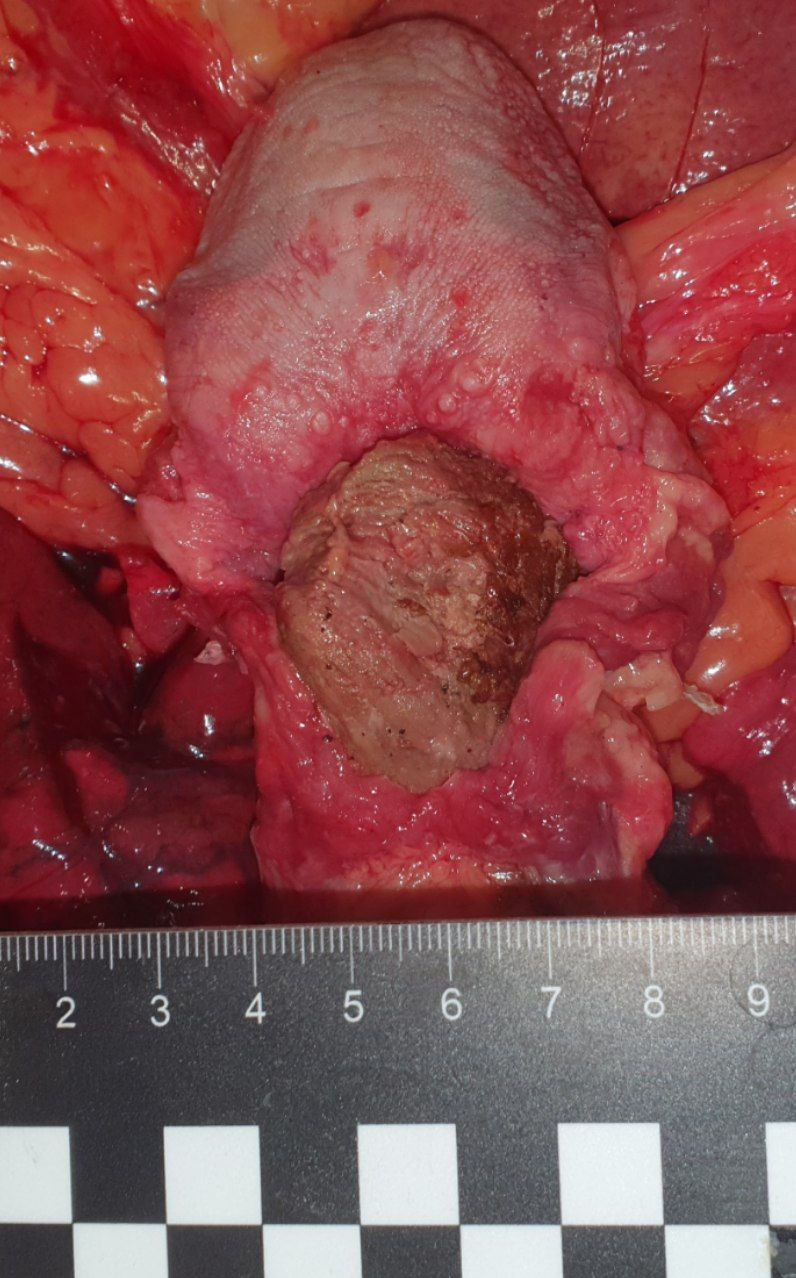

IMG_20260417_201344_300.jpg

Кусок жареного мяса в просвете гортаноглотки. Обтурационная асфиксия.

В общем, очевидная истина — мы не птички и не змейки, которые могут проглотить целиком рыбину или сожрать капибару как анаконда какая-нибудь. Жуём. не спешим.